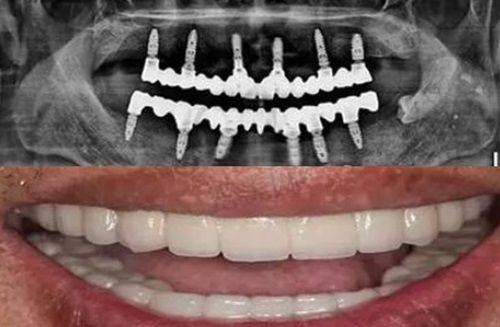

种植牙:对于缺失牙齿的患者,门诊部提供种植牙服务。采用国内外精良的种植系统,由经验多的医生进行操作,确保种植成效的稳定性和美观性。种植牙不仅能够修复牙齿的功能,还能提升患者的面部美观度。

数字化口腔全景机:这是一种精良的口腔影像设备,能够快速、正确地拍摄口腔全景图像。通过全景机拍摄的图像,医生可以清晰地了解患者牙齿、牙槽骨等口腔结构的情况,为诊断和治疗提供重要的依据。其优势在于成像速度快、图像清晰,能够减少患者的拍摄时间和辐射剂量。

口腔CBCT:与传统的X光片相比,口腔CBCT能够提供三维立体的口腔影像。它可以严谨地显示牙齿的内部结构、牙槽骨的密度和形态等信息,对于种植牙、正畸等复杂的口腔治疗具有重要的指导意义。医生可以通过CBCT制定更加精细的治疗方案,提高治疗的成功几率。